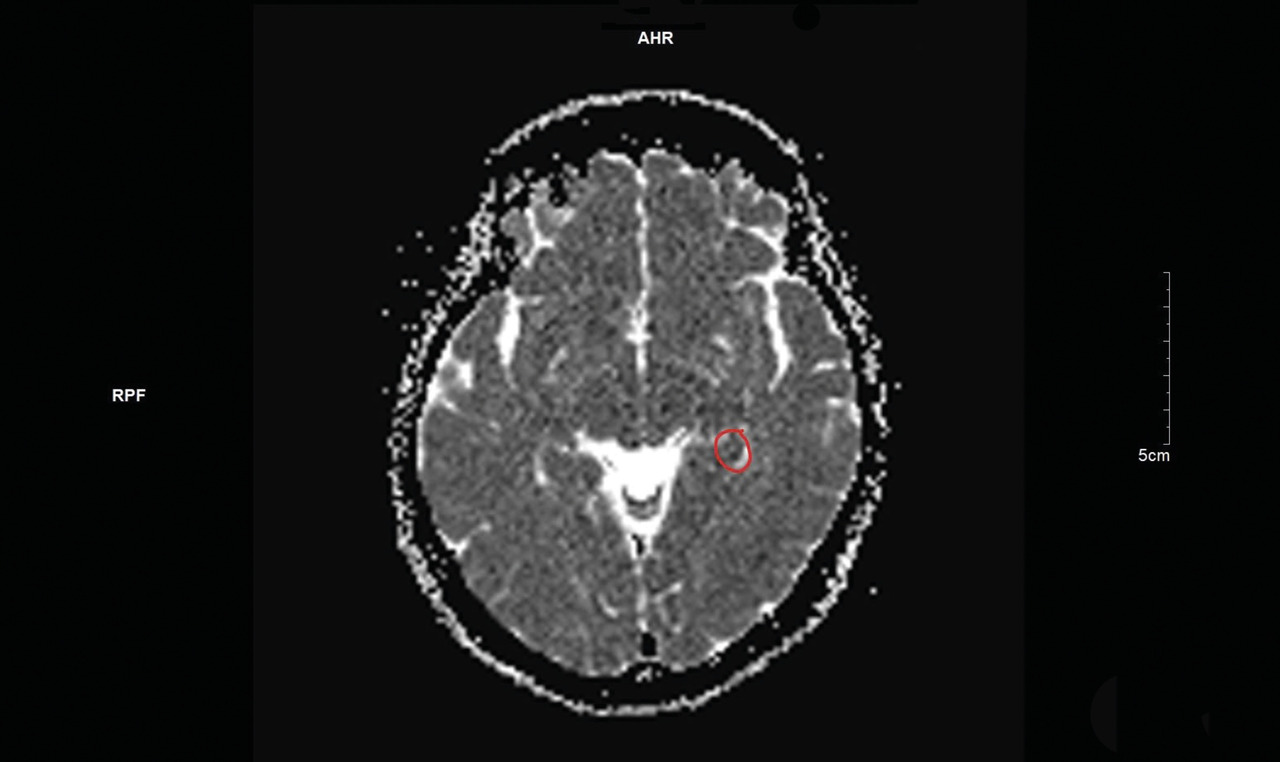

Une imagerie par résonance magnétique (IRM) cérébrale est réalisée quarante-huit heures après l’épisode, mettant en évidence un hypersignal punctiforme en séquence diffusion (fig. 1) et en hyposignal ADC (apparent coefficient diffusion) [fig. 2] localisé à la partie interne du lobe temporal gauche.

L’IRM permet de mettre en évidence les signes caractéristiques à la partie interne du lobe tempo­ral (hypersignal diffusion et hy­posignal ADC), avec une détection optimale deux et trois jours après l’épisode. Il est important de préciser au radiologue la nécessité de réaliser des coupes fines de la région.